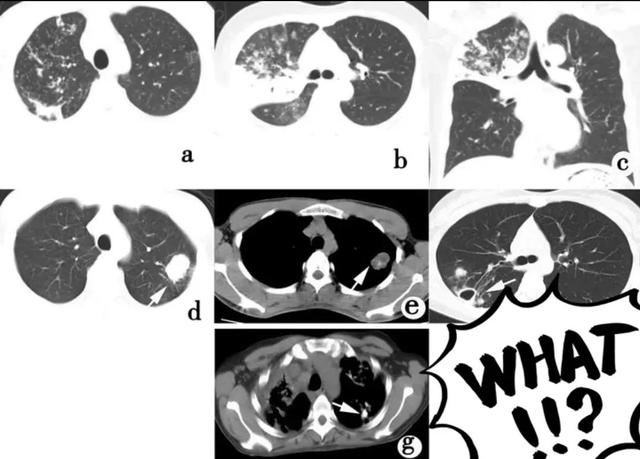

肺结核的分型诊断标准,肺结核的分型及影像学表现

继发型肺结核CT表现

a.浸润性肺结核:右上肺斑片状实变影,周围可见条索状及结节状影;b、c. 干酪性肺炎:右上肺见大片状实变影。边界模糊,周围可见多发小片状实变影;d、e. 结核球:左上肺见团块状影,内见点状钙化灶;f.右上肺见一薄壁空洞,周围见斑片状卫星灶;g.两上肺见斑片状及条索状影,左上肺可见钙化灶,右上胸膜增厚明显;